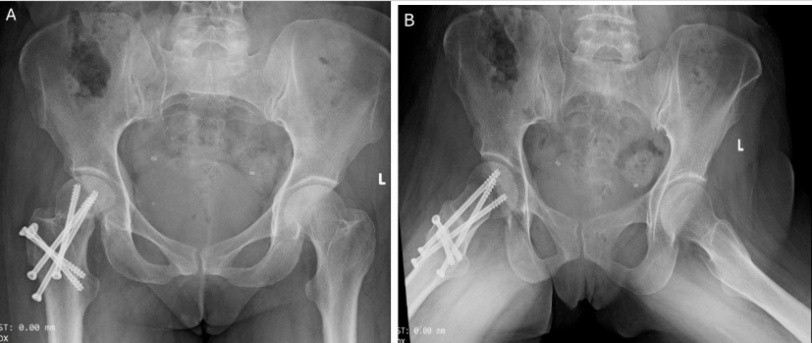

Sutures were removed after 2 weeks, and the wound had healed well. The patient was followed up monthly for the first 6 months, and then every 3 months up to 1 year. Partial weight-bearing was initiated at 8 weeks, progressing to full weight-bearing by 12 weeks, at which point complete fracture union was achieved (Fig. 5).

Figure 5: Post-operative X-ray at 3 months showing union at femoral neck fracture (a) anteroposterior and (b) lateral views.

At the 18-month follow-up, there were no signs of avascular necrosis of the femoral head, and the patient was able to walk comfortably with a good range of motion, and the patient’s Harris Hip Score was 96.80, signifying an excellent functional outcome (Figs. 6 and 7).

Figure 6: Post-operative X-ray at 18 months showing no sign of avascular necrosis of the femoral head in (a) anteroposterior and (b) lateral views of the right hip.